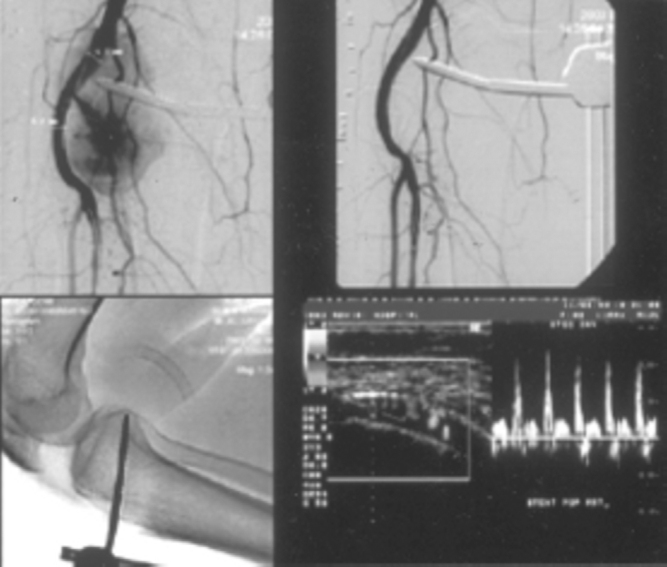

Fig. 3B.

DSA of right kidney in same patient shows pseudoaneurysm. Post embolisation DSA images reveals obliteration of pseudoaneurysm. Note the distribution of coils along the renal artery on CT abdomen.

Endoluminal repair by stent graft is an emerging strategy in treatment of pseudoaneurysms. A stent graft is a metallic stent with a biologically compatible polymer cover usually made of polyester or polytetrafluoroethylene. The polymer cover limits myointimal ingrowth along the length of the treated segment, improving patency. In our series, Hemobahn/Viabhan endoprosthesis was used in five cases (Fig. 4A, Fig. 4B). The Hemobahn endoprosthesis is flexible, self-expanding, endoluminal prosthesis with an expanded polytetrafluoroethylene (ePTFE) tube inside a nitinol sinusoidally shaped helically wrapped stent [11].

Fig. 4A.

Doppler study of right popliteal region in a patient following fracture tibia, stabilized with screws shows popliteal artery pseudoaneurysm. Note the screw tip within the pseudoaneurysm. Axial CT shows extent and size of pseudoaneurysm. Sagittal MPR reveals the screw traversing the tibia with its tip within the pseudoaneurysm

Fig. 4B.

DSA image of right popliteal artery with arterial leak into pseudoaneurysm. DSA after stent graft shows complete isolation of pseudoaneurysms with patency of popliteal and tibial arteries. Plain film of right knee joint in flexion shows normal configuration of stent graft with no kinking.